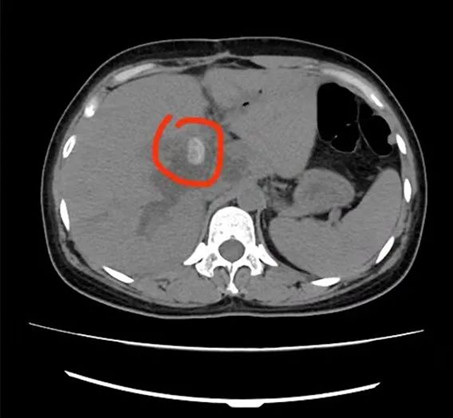

5分鐘后,楊林副主任便趕到急診科,這時(shí)腹部CT結(jié)果已經(jīng)出來(lái):肝內(nèi)外膽管多發(fā)結(jié)石,肝內(nèi)外膽管擴(kuò)張;膽囊切除后;肝門(mén)下緣胃大彎旁囊性病變伴高密度影。

術(shù)前

術(shù)后

據(jù)悉,術(shù)中共取出19顆“石子”?;颊哌M(jìn)入重癥醫(yī)學(xué)科(ICU)觀察,隨后病情穩(wěn)定后轉(zhuǎn)入普外科病房繼續(xù)進(jìn)行治療,目前患者病情穩(wěn)定,不日即可康復(fù)出院。